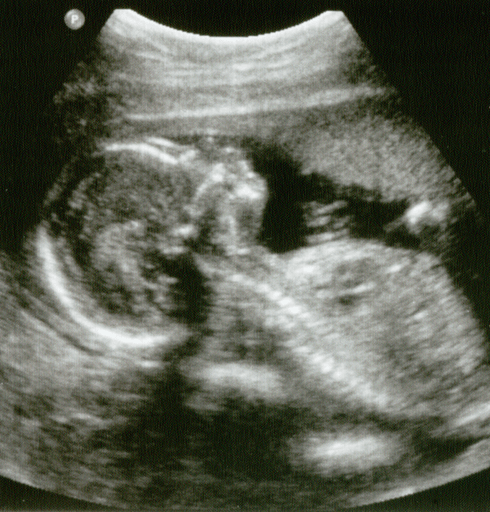

When I was pregnant with Theo, I had my first ultrasound at 11 weeks gestation. I’d had some bleeding early on in my pregnancy, and, going into the ultrasound, I was terrified that they would find something wrong with him.

The minute the probe hit my belly, though, itty bitty Theo appeared on the screen. He was perfect; all blobby torso-head and stubby little limbs. When I saw him, I laughed with relief, and when I laughed, he jumped, waving his arms and legs in protest. We watched, mesmerized, as he wriggled around, his heart a flickering beat in the middle of his chest.

To me, in that moment, he went from being two-lines-on-a-pregnancy-test-morning-sickness-and-achy-breasts to being an actual little person. Seeing him on the screen made me fall in love with him.

And this is the problem: if my feelings could make me believe that a baby the size of a fig is a person, then someone can likely argue that any fetus, at any gestational age, is a person. If I, a staunchly pro-choice feminist can, under the right circumstances, believe that a fetus of 11 weeks gestation is a person, then it’s not impossible for our government to come to the same conclusion.